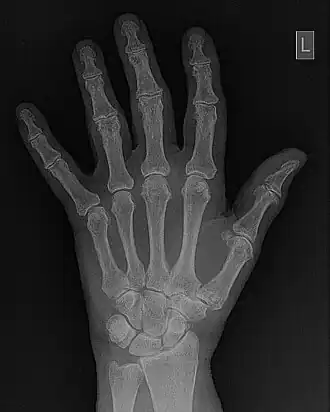

Spatial Frequency Processing

- Fourier methods are used in digital image processing to enhance the display of image detail. Here the 2D-FFT is manipulated so that certain spatial frequencies can be boosted in the displayed image to enhance, for instance, the display of the surrounds of features, e.g. Edge Enhancement. Suppression of features is also possible using this technique to generate a smoothing of image detail to reduce their prominence and the mottled appearance of image noise. The general process is illustrated in Figure 5.9. It involves transforming the image data into the spatial frequency domain using the Fast Fourier Transform (FFT), manipulating these frequencies by applying a spatial-frequency filter and then re-transforming the data back into the spatial domain, using the Inverse FFT (IFT). Parameters which define the filter generate different effects.

- Fourier filtering is illustrated in more detail in Figure 5.10. The wrist/hand radiograph of the Figure 5.6 is again used for this illustration. You might remember that its 2D FFT was discussed in an earlier chapter. The filter is shown in panel (c) of the figure in the form of a two-dimensional image. It can be seen that the image data is symmetrical around the centre (i.e.isotropic) where its pixel values are relatively low. Outside this central dark region, a halo of bright pixel values dominates the image as the pixel value trails off slowly towards the periphery. An amplitude profile through this image is shown in panel (d) to further illustrate the effect. The filter can be used to modify the 2D-FFT by multiplying it by the filter values, for instance, to form a filtered 2D-FFT - as shown in panel (e). The Inverse FFT (IFT) of this data is then reveals the filtered image - see panel (f). Given that certain spatial frequencies have been amplified while others have been suppressed with this type of filter, it is called a Bandpass filter.

- Note that spatial frequency filters can also be classed as Low-Pass (giving image smoothing) and High-Pass (giving edge enhancement). Here the filter function as illustrated in panel (d) of the figure would have a form which allows low or high frequencies to be accentuated while high or low frequencies, respectively, are suppressed. Parameters which can control the transition between accentuated and suppressed frequencies are:

- the value at which the transition occurs, called the Cut-Off Frequency, for example, and

- the rate at which the transition changes - either abruptly or gradually - called the Order or Power of the filter function.